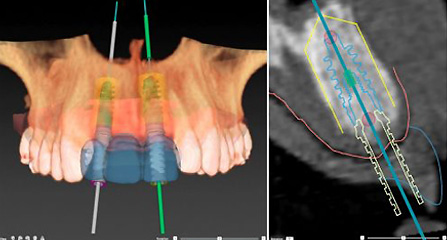

麦芽口腔着眼于全链条的数字化诊疗解决方案,与德国Kavo、瑞典Nobel、韩国奥齿泰、中国康泰健等国际知名齿科品牌合作,建立“深圳数字化口腔联盟”,应用全数字化口腔模式,从CBCT数据提取、AI口扫取模、AI智能口腔体检、数字化分析模拟与方案设计、3D打印、CAD/CAM椅旁加工以及手术模拟导航等,全流程打通数字化口腔精确诊疗的各个环节,实现麦芽数字化口腔诊疗体系新升级。

动态导航监测 精确控制植入路径